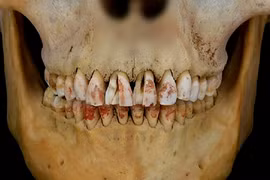

Cách đây hàng ngàn năm, người xưa đã sử dụng những công cụ thô sơ để chăm sóc, làm đẹp răng. Trong số này có trường hợp trồng răng giả sớm nhất ở khu vực Tây Âu từ khoảng 2.300 năm trước.